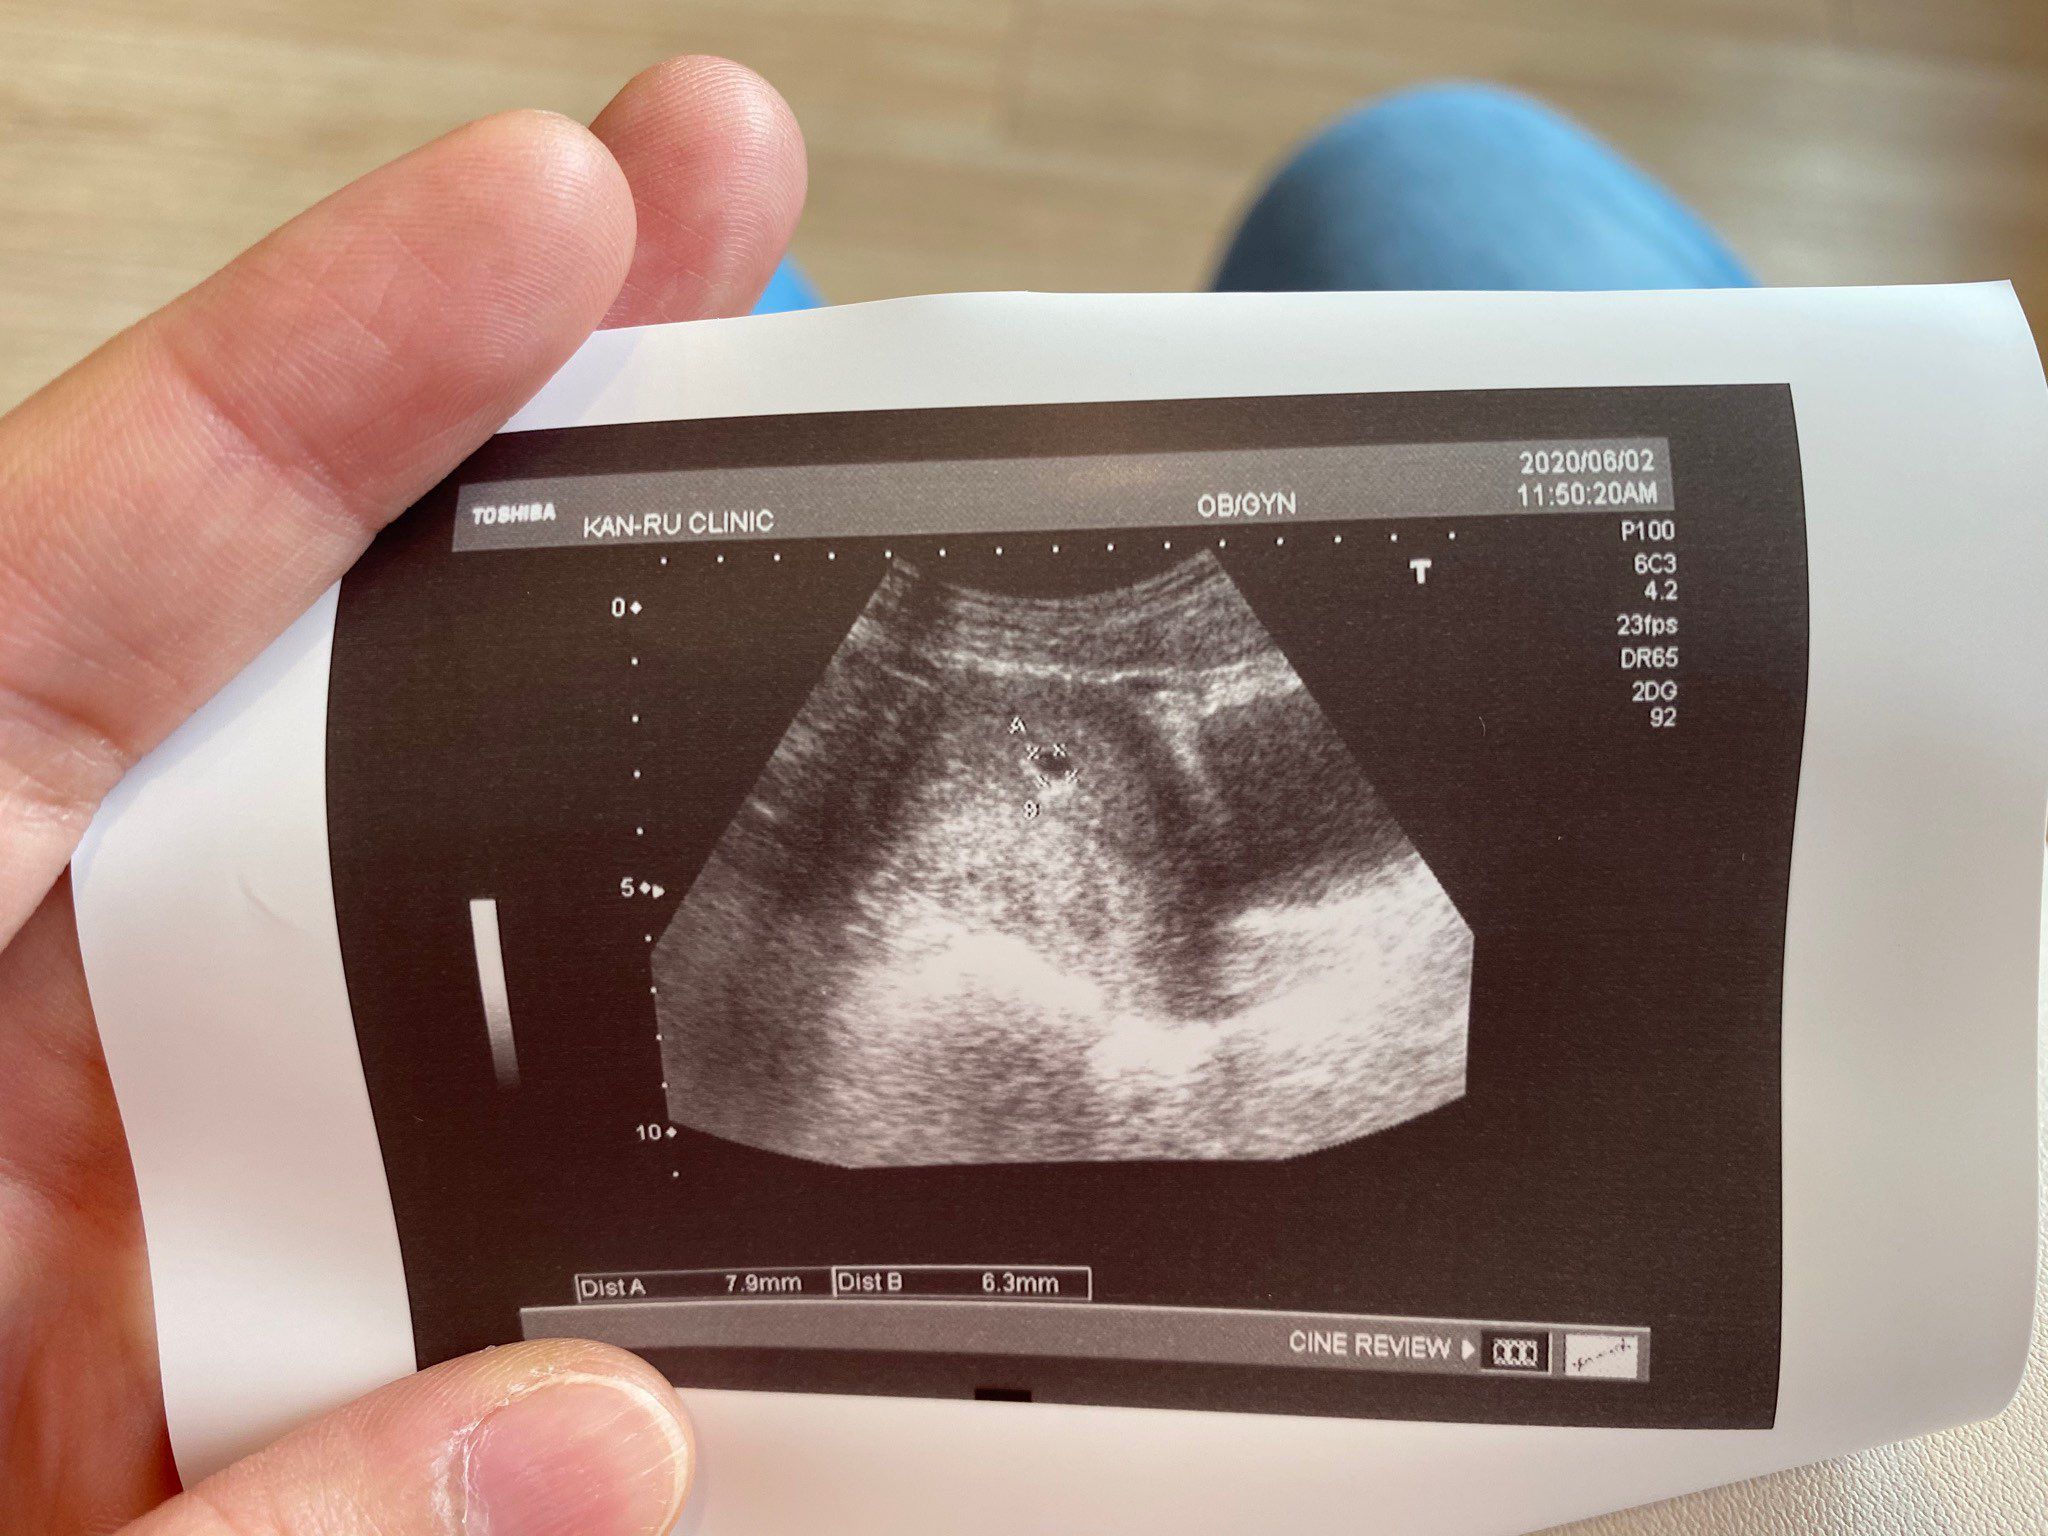

照到胚胎5週囉~

照到可愛的胚胎5週了!

但目前沒有任何感覺

沒有孕吐 只有偶爾肚子悶悶的

請問這樣是正常的嗎😅